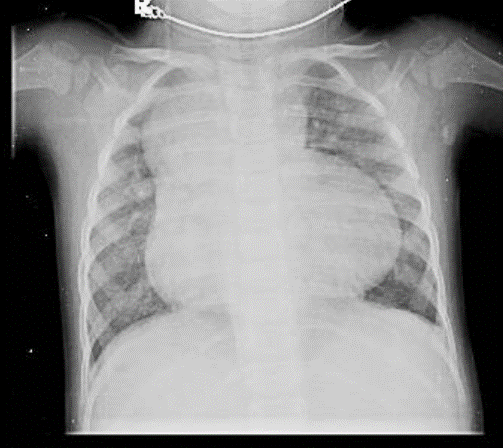

Hãy phân tích tình huống Nữ 6 tuổi Situs inversus, thiểu sản val 2 lá và thất (T), teo val động mạch phổi, hở val nhĩ thất trung bình

1- Bóng tim lớn 2-Trung thất trên rộng